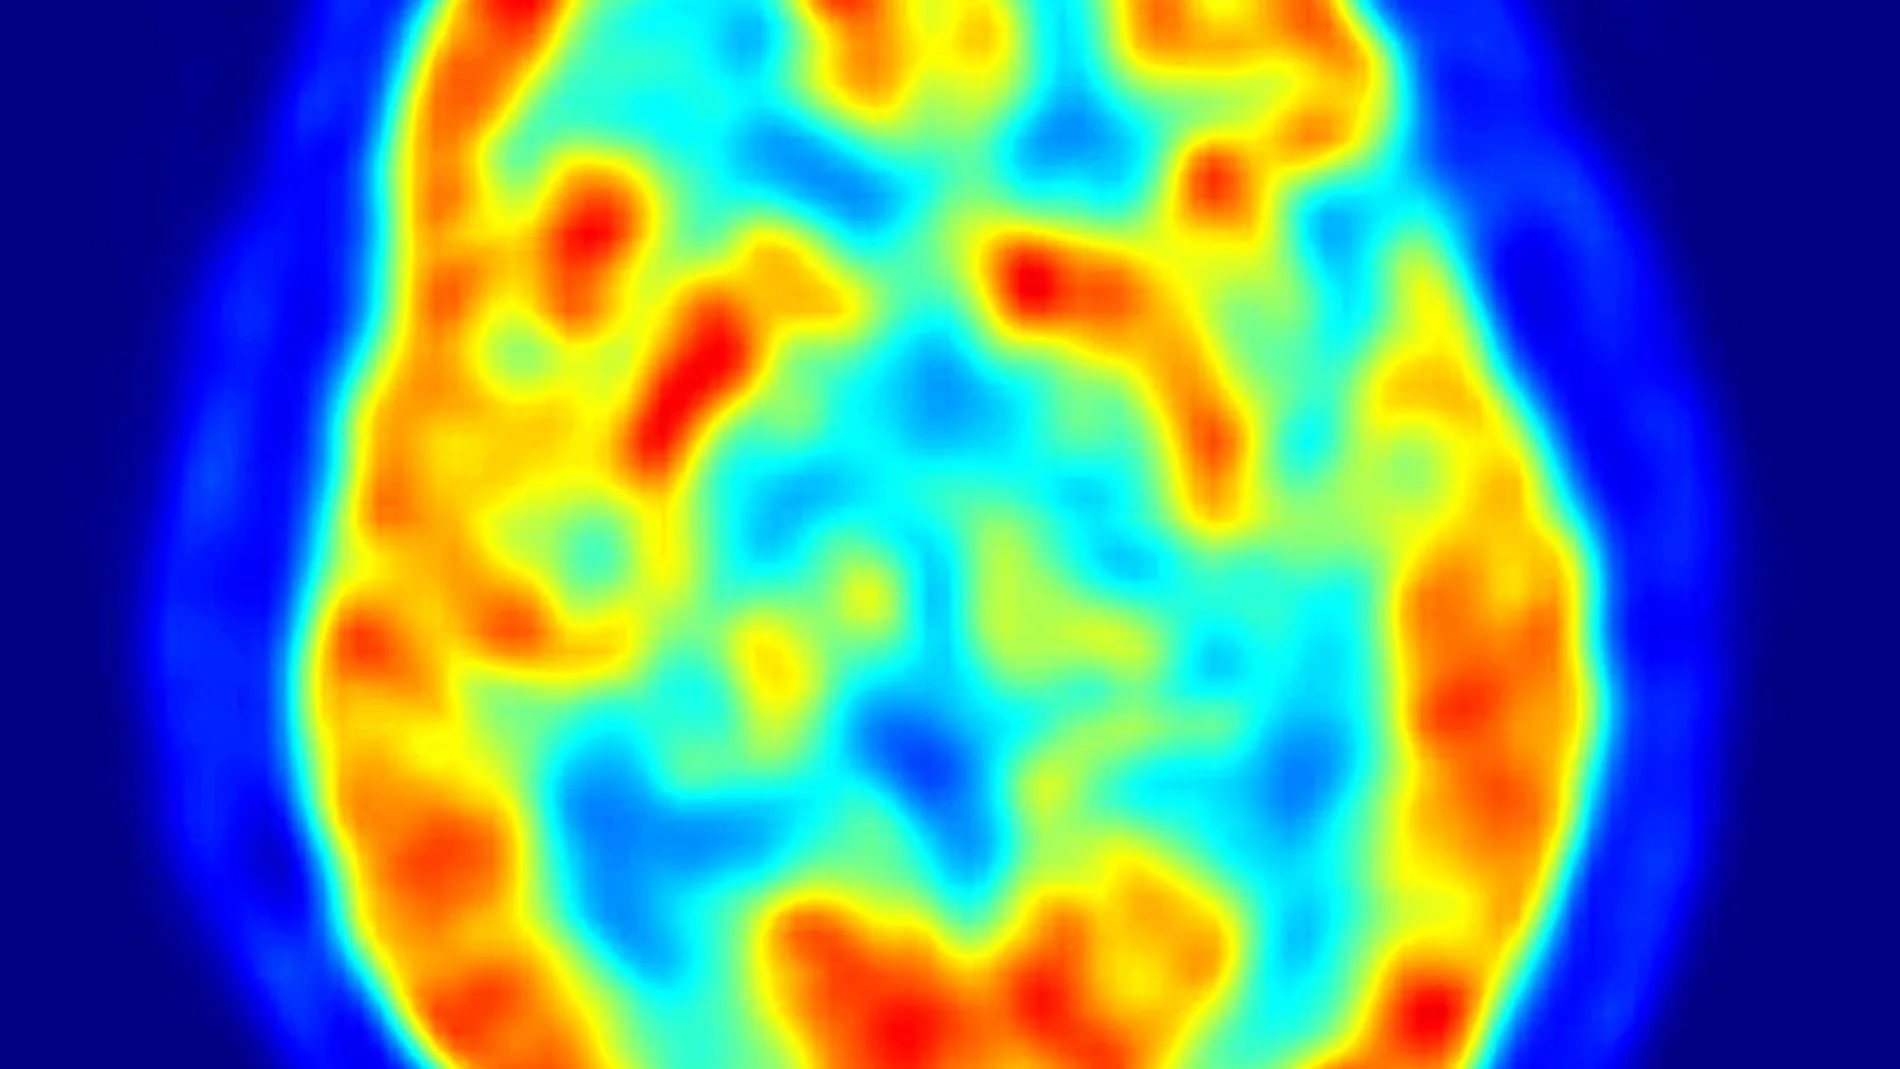

El Parkinson es un trastorno cerebral que causa movimientos involuntarios o incontrolables, como temblores, rigidez y dificultad con el equilibrio y la coordinación. Estos se producen cuando las células nerviosas de los ganglios basales, un área del cerebro que controla el movimiento, se deterioran y/o mueren. Normalmente, estas células nerviosas o neuronas producen una importante sustancia química cerebral conocida como dopamina. Cuando las neuronas mueren o se deterioran, producen menos dopamina, lo que provoca los problemas de movimiento asociados con la enfermedad.